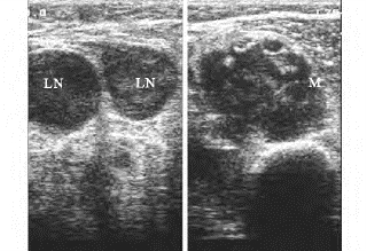

2.声像图表现 良性骨肿瘤呈占位效应,回声强度依组织特性不同而有所变化,腘窝囊肿、腱鞘囊肿等表现为局部圆形或椭圆形,边界较清无回声区,后方伴声增强,实质性呈膨胀性生长,边界清晰,有假包膜存在,骨膜回声连续,内部回声均匀。一般不侵犯软组织,无骨膜改变,透声性好,无衰减,血流不丰富。恶性骨肿瘤包块多表现为外形不规则,内部回声为低回声或强弱不等回声(图35-11),分布不均匀,边缘不清楚,后方有衰减,内部血流较丰富,同时有出血坏死者伴无回声区。骨质被破坏,骨质中断处回声杂乱,骨皮质连续性中断或变薄,骨膜增厚断裂。

图35-11 骨肿瘤声像图

左图为淋巴结肿大,右图为低回声病变